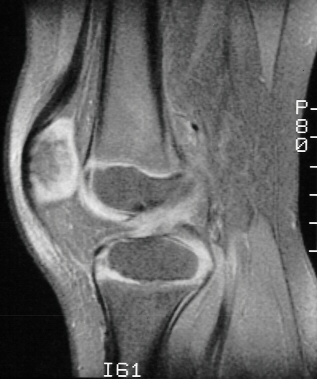

The patient was sent for physical therapy and an MRI to rule out ligament

or meniscal injury. MRI was read by radiologist as anterior cruciate ligament

tear and small medial meniscal tear

- MRI : 97% accurate compared to arthroscopy in diagnosing ACL tears

(ages 14-69, average age 33)

Less accurate in diagnosing tears in children